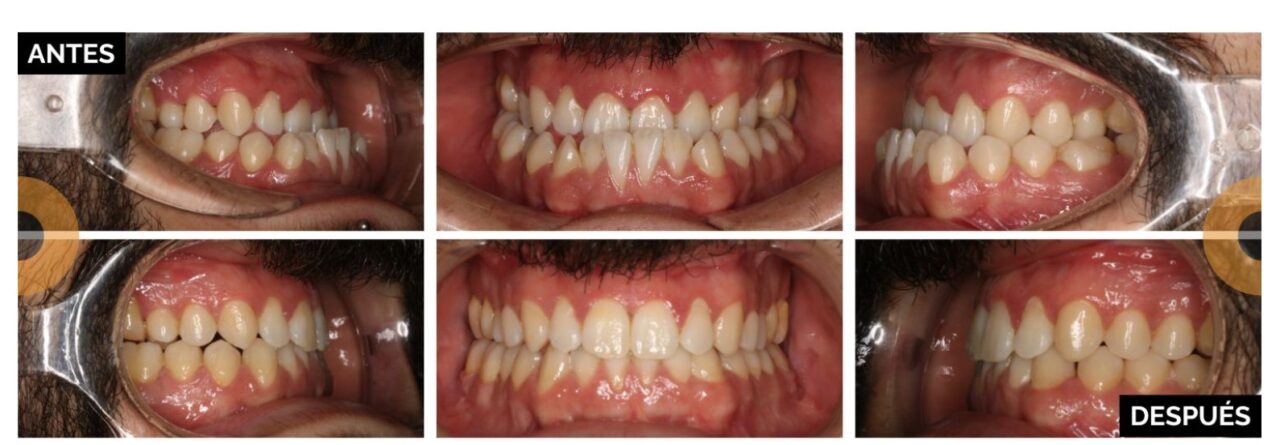

La cirugía ortognática trata las discrepancias esqueléticas severas que afectan a la posición de los dientes y la estructura ósea facial. A diferencia de la ortodoncia, que solo mueve piezas dentales, la cirugía ortognática desplaza y corrige la posición de las bases óseas del maxilar superior y/o la mandíbula.

- Grandes maloclusiones dentales: mordida abierta anterior, mordida cruzada posterior, clases II con resalte dental anterior aumentado o clases III con resalte dental anterior invertido.

- Así mismo, la cirugía ortognática mejora drásticamente la estética facial al reposicionar los maxilares, logrando un perfil más armónico, un mentón definido y una sonrisa equilibrada.